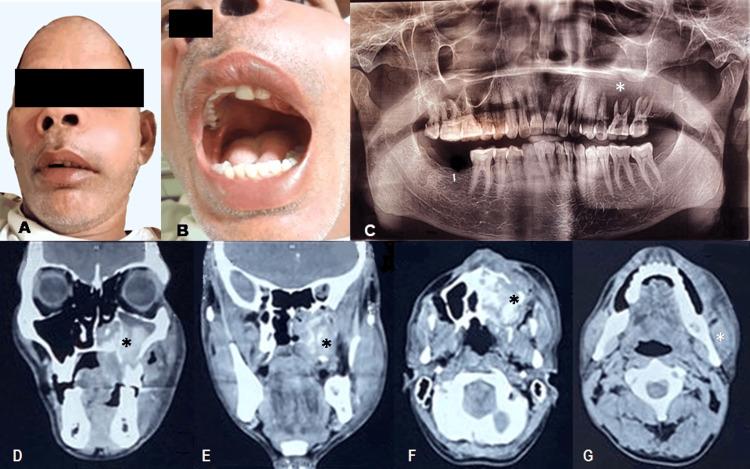

Salivary duct carcinoma is a rare, aggressive salivary gland neoplasm that is difficult to diagnose preoperatively. It shows limited clinical resolution of recurrent or metastatic cases after conventional conservative chemotherapy and/or radiation therapy. Here, we present the case of a 42-year-old man with high-grade carcinoma of the salivary gland with morphological and immunohistochemical characteristics consistent with salivary duct carcinoma, along with a succinct literature assessment.

涎腺导管癌是一种罕见的、侵袭性唾液腺肿瘤,术前难以诊断。在传统的保守化疗和/或放射治疗后,复发或转移病例的临床缓解有限。在此,我们报告一例42岁男性的高级别唾液腺癌病例,其形态学和免疫组化特征与涎腺导管癌一致,并对相关文献进行简要评估。